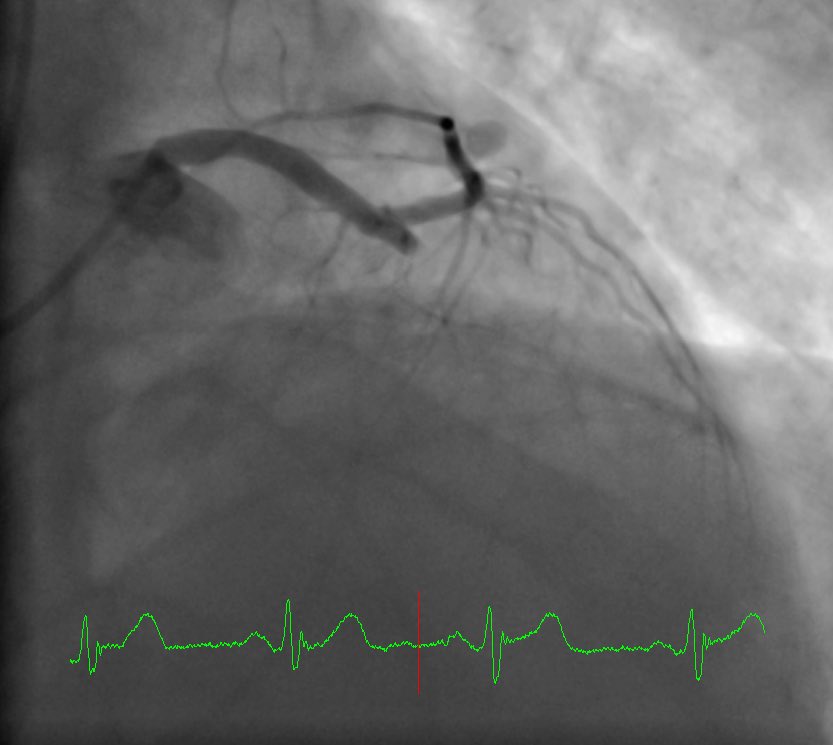

Ostial LCX is 99%, LM, LAD, Diag as you see. How do you tackle ⁦@ShariqShamimMD⁩ ⁦@Asaadakbarkhan

CheemaFACC's tweet image. Ostial LCX is 99%, LM, LAD, Diag as you see. How do you tackle ⁦@ShariqShamimMD⁩ ⁦@Asaadakbarkhan⁩